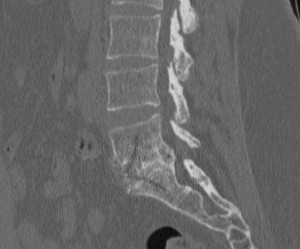

fusion complète

Fusion intervertébrale complète

Coupe Scanner de profil